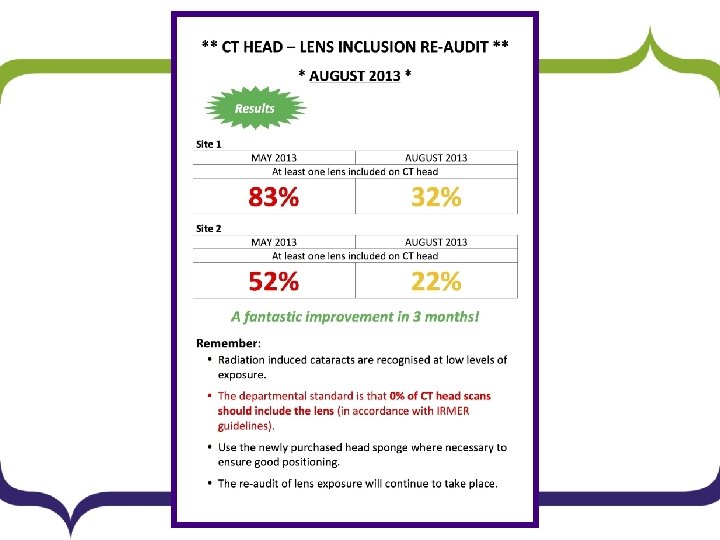

Measuring Quality Improvement Success: RE-AUDIT

Results Site 1 Site 2 Number Av Age % Both 11 79. 1 22% 1 68 2% Single 5 61 10% 10 76. 7 20% Neither 33 54. 9 67% 39 70. 7 78% Total 49 60. 5 100% 50 71. 9 100% • At Site 1, at least one lens was exposed in 32% of patients (16/49) vs. 83% previously. • At Site 2, at least one lens was exposed in 22% (11/50) vs. 52% previously. • Across the entire trust, at least one lens was exposed in 27% (27/99) vs. 67% previously.

Conclusions § Compliance has improved. § Positive steps have been made – there remains § scope for improvement. Scanning at the Site 2 remains closer to the standard than at Site 1.

Further Recommendations § The positive results of the audit have been emailed to the radiographers and continued compliance is to be encouraged in departmental newsletters. § A further poster displaying the results of the audit has been displayed in the CT control room and staff room. § Re-audit will be performed in 9 months to monitor longterm compliance and the project has been added to the annual audit list.